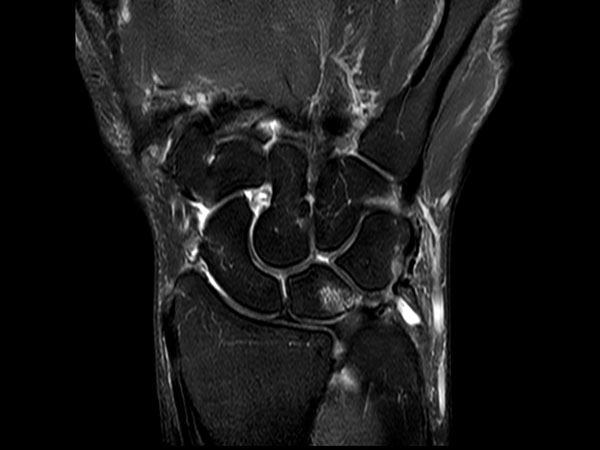

Comprehensive wrist imaging